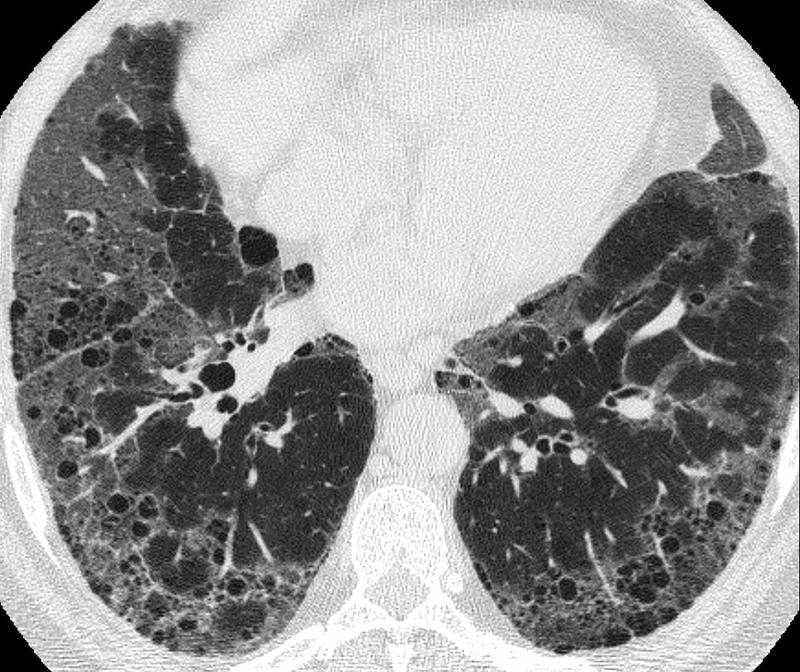

Gallery Pulmonary Fibrosis IPF Case 8e

Case 8e